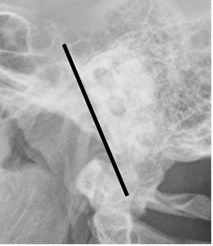

También se debe dibujar la línea clivus-odontoidea. Se traza a lo largo del clivus, por detrás del dorso de la silla turca.Normalmente debe pasar entre el tercio medio y anterior, de la punta de la odontoides. (2). (Fig 189).

Fig 189. Alineación unión craneoespinal.

Rx lateral. Línea sobre el dorso del clivus, que cruza la odontoides.